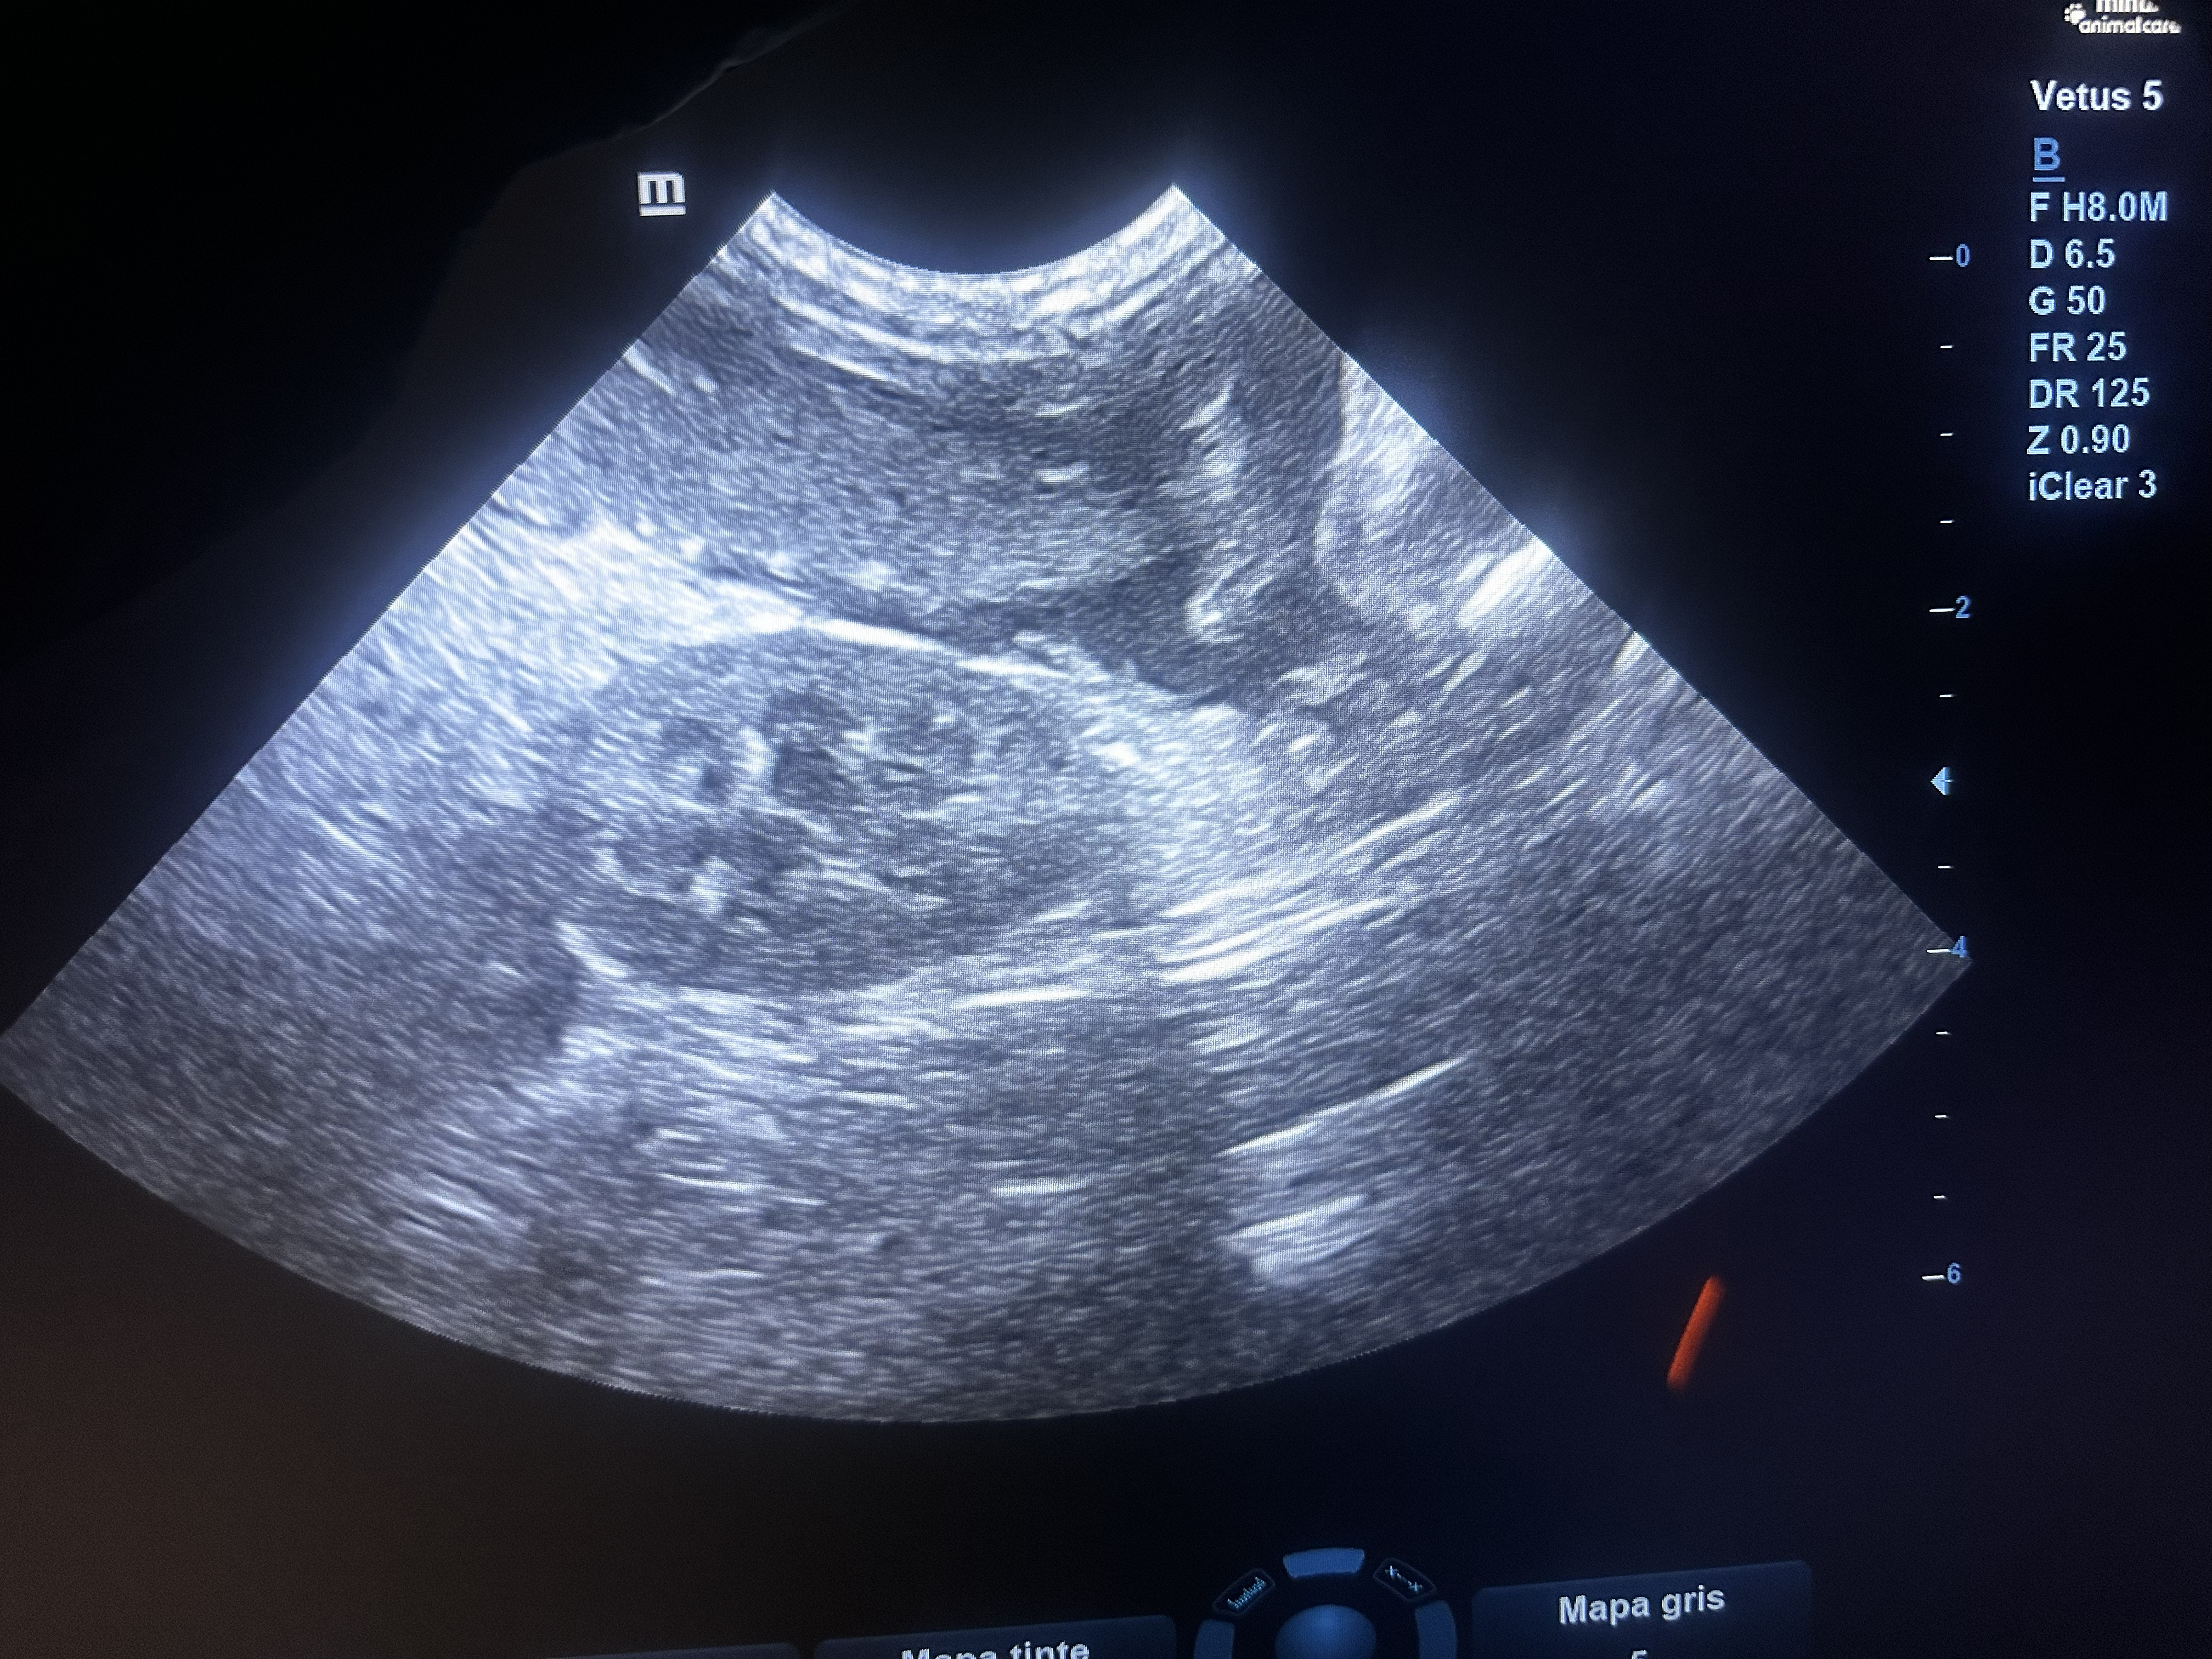

Dentro de CENEV contamos con especialistas dedicados al área de imagenología, dedicados al diagnóstico por pruebas como ultrasonido abdominal, radiología de tórax y abdomen, entre otras.

Nuestros equipos y personal especializado permiten estudios rápidos y de alta calidad para apoyar el diagnóstico clínico.